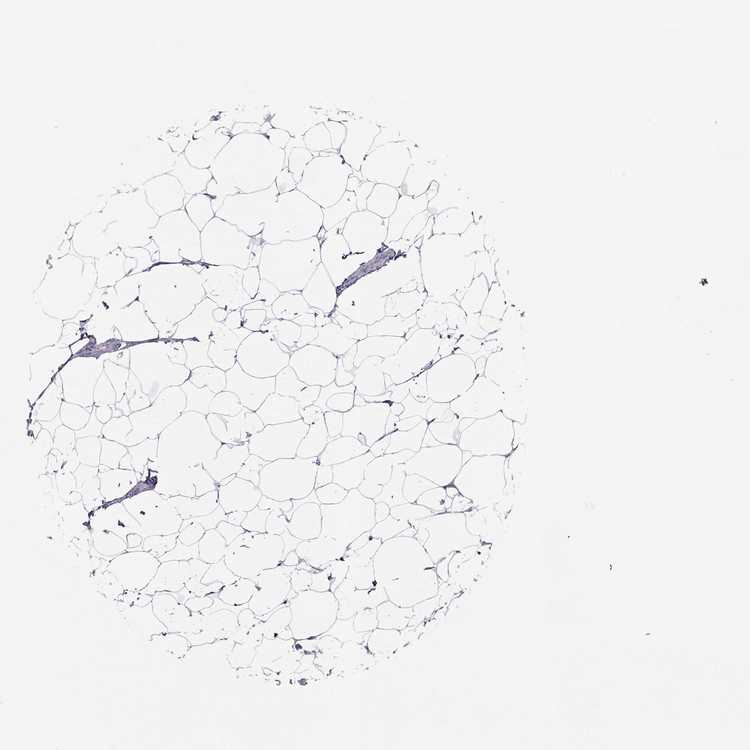

BREAST - Antibody stainingi

Antibody staining in the annotated cell types in the current human tissue is reported as not detected, low, medium, or high, based on conventional immunohistochemistry profiling in selected tissues. This score is based on the combination of the staining intensity and fraction of stained cells.

Each image is clickable and will lead to virtual microscopy that enables deeper exploration of all samples and also displays staining intensity scores, fraction scores and subcellular localization as well as patient and tissue information for each sample.

Antibody HPA046810

Adipocytes Not detected

Glandular cells Not detected

Myoepithelial cells Not detected